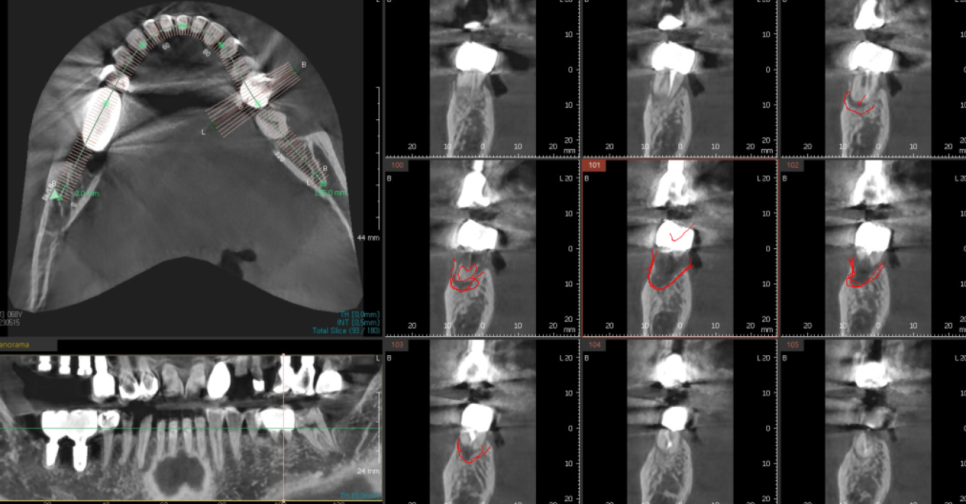

굳이 잇몸을 절개하지 않아도

1)ct를 통하여 충분히 잇몸뼈 상태를

분석할 수 있기 때문에

불필요한 불편감은 드리지 않습니다.

23.09.11

예측도 가능하여

모의 수술을 진행해보기 때문에

무절개 임플란트 수술이 가능한건데요.